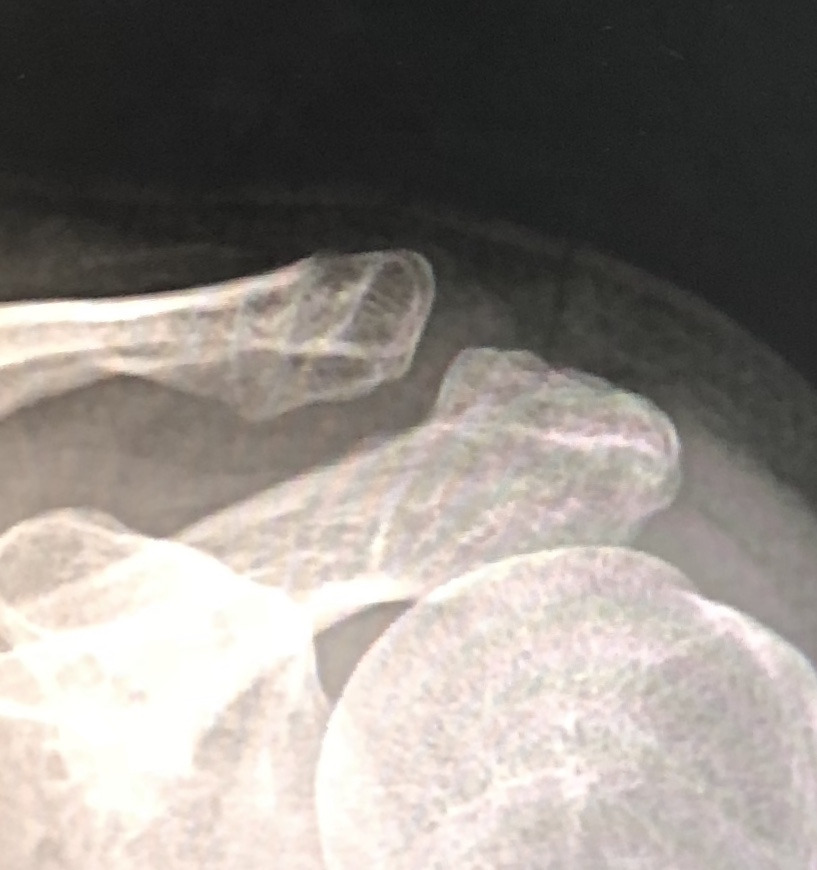

16주차

그리고 16주차 아침에 병원 진료에서 엑스레이를 확인했다. 의사는 이제 엑스레이 그만 찍어도 된다고 하시며, 팔을 들어보라시더니 도수치료는 좀 더 받아야겠다고 말했다. 내가 생각해도 지난 3주간 큰 진전이 없는 듯했다. 의사는 다음달에 보자는 말을 남겼지만 사실상 이젠 더 진료를 보지않아도 된다는 걸 나는 직감했다. 현재 상태에 나쁜 방향으로 이변이 없다면 말이다.